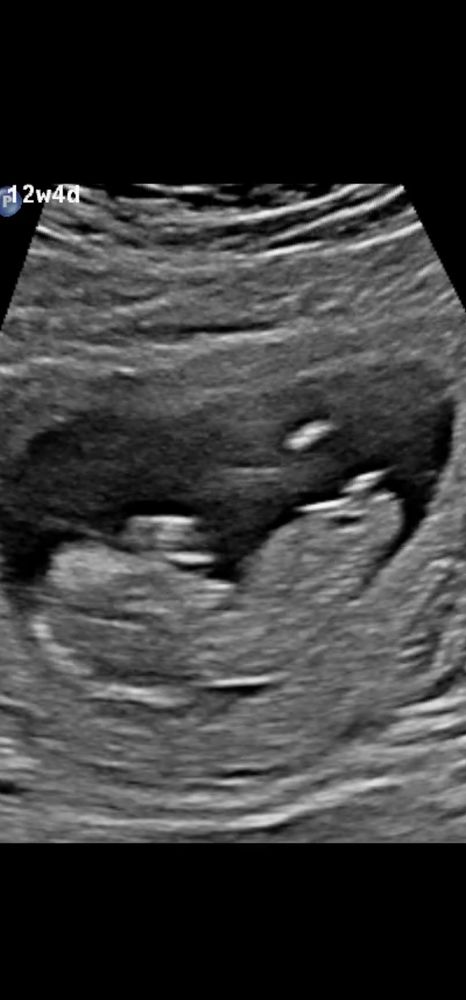

Первый скрининг, половой бугорок? 😁

Фотография ⬆️

Сегодня был первый скрининг, всё хорошо у малыша/малышки, но у меня теперь маленький нерв весь день заставляет разбирать этот половой бугорок. Во время УЗИ я будто увидела бугорок параллельный, на девчонку, а смотрю на фотографии - вижу под углом, на мальчишку 😁